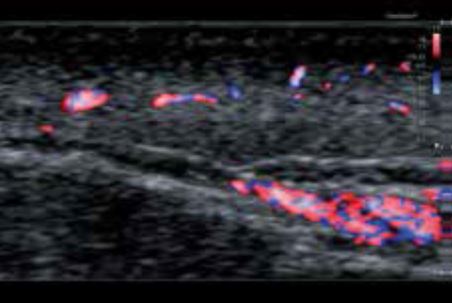

Мікоз фунгоїдний (шкірна Т-клітинна лімфома)

У випадку грибкового мікозу, де товщина ураження становить лише 0,4 мм, надвисокочастотний датчик може чітко візуалізувати злегка потовщений шар ( мал. 4а). Враховуючи розмір, його зазвичай складно спостерігати у відтінках сірого. Після застосування супермікросудинної візуалізації (SMI) ураження чітко відмежоване від нормальної ділянки шкіри, оскільки воно, безумовно, є гіперваскулярним ( мал. 4б). На мал. 4в показано 3D-зображення двох вогнищ ураження. Аваскулярна ділянка між ураженнями представляє нормальну шкіру.

а) Сірошкальне зображення

б) cSMI

в) cSMI з використанням Smart sensor 3D

Малюнок 4. Фунгоїдний мікоз (шкірна Т-клітинна лімфома)